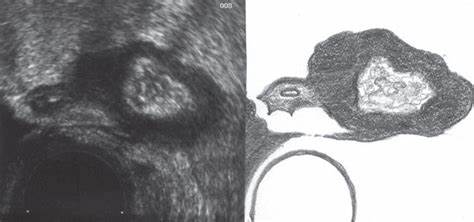

Картинка 54: Боли в правом паху Дивертикулез сигмовидной кишки. Вагинальное УЗИ